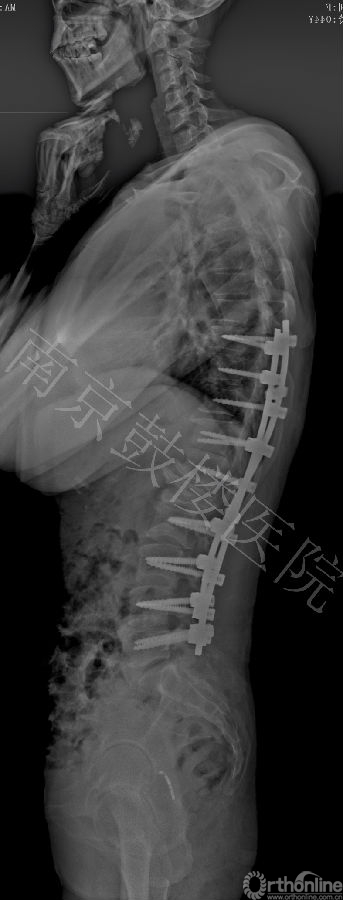

近日,南京鼓楼医院成功运用后路全脊椎截骨术和CDH Solera内固定矫形技术治疗一例先天性脊柱侧后凸成年患者。此为Solera内固定系统在中国的首例手术。

Solera系统是最新一代的CD Horizon产品,新增了独特的钴铬钉头设计和双螺纹设计,提高了钉头强度和螺钉把持力,固定棒有多种直径和材质供选择。该系统近年在欧美国家逐渐推广应用。

本例女,44岁,因严重的脊柱侧后凸畸形造成躯干塌陷,接受全脊椎截骨术和Solera内固定系统矫形手术,矫正率高达82%,无并发症发生。患者对手术效果非常满意。